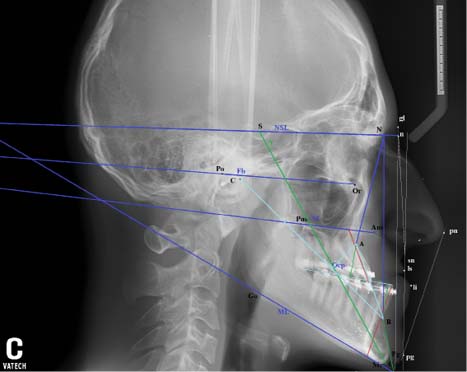

При оценке направления роста лицевого скелета растущего пациента большинство авторов считают базовой величину суммарного угла по Bjork, значение которого указывает на нейтральный (396°), вертикальный (>396°) либо горизонтальный (<396°) тип роста. Результат нашего исследования по способу Bjork (∠NSAr+∠SArGo+∠ArGoMe=118,8+138,8+132,6=390,2°) оказался характерным для горизонтального типа роста лицевого скелета пациента К. Метод по Jarabak дал неоднозначный результат (рис. 3).

Рис. 3. Прогнозирование направления роста лицевого скелета на профильной телерентгенограмме головы пациента К. по методам Jarabak и Bjork